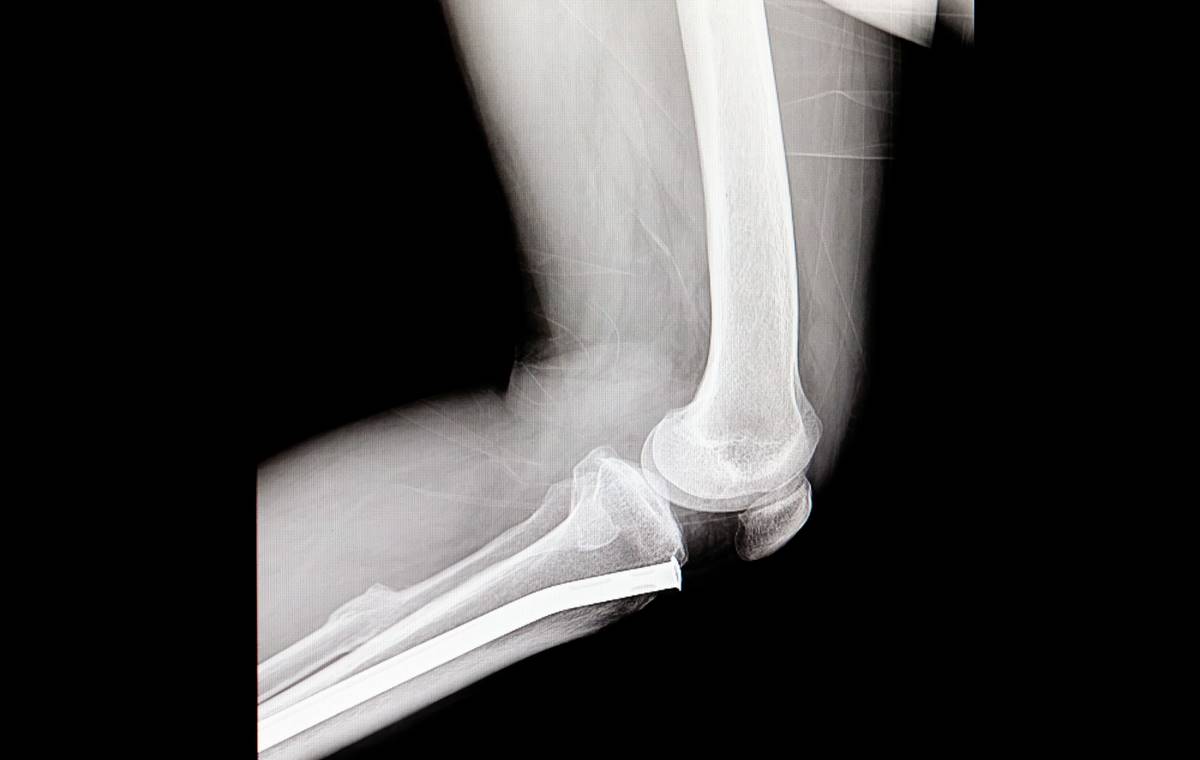

Кістки, зламані внаслідок аварій, зазвичай загоюються самостійно. Але коли перелом надто серйозний або потрібно видалити кісткову пухлину, хірурги вставляють імплант — металевий, керамічний або шматок власної кістки пацієнта. Кожен із цих варіантів має суттєві недоліки: власна кісткова тканина потребує окремої операції для забору, металеві протези надто жорсткі й з часом розхитуються.